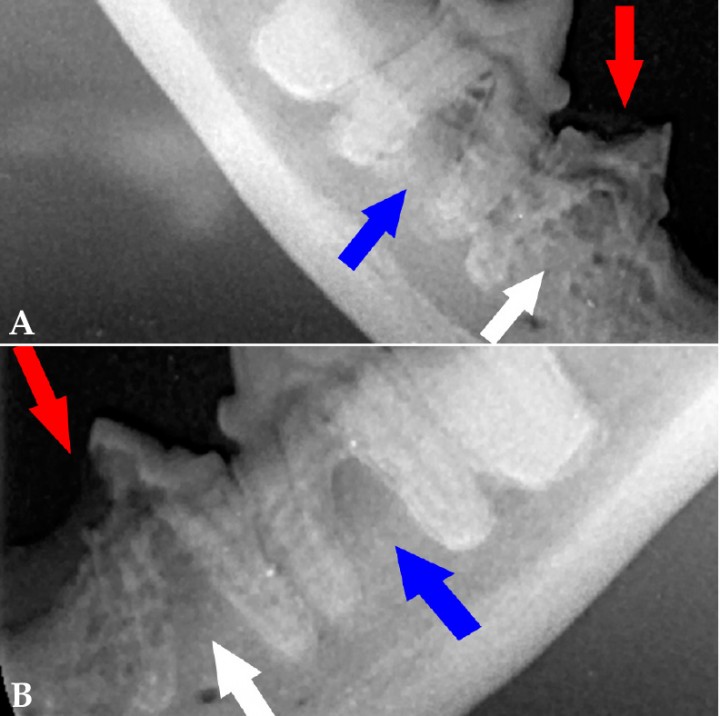

<p>(<strong>A</strong>) Radiografía dental intraoral de los premolares y molar mandibulares derechos. Se observa pérdida de tejido duro del diente a nivel de la cara distal de la corona de 407 (flecha roja) y cierto grado de anquilosis a nivel radicular (flecha blanca), hallazgos radiológicos compatibles con RD de tipo 3. Existe cierto grado de anquilosis a nivel radicular en 408, compatible con RD tipo 2 (flecha azul). (<strong>B</strong>) Radiografía dental intraoral de los premolares y molar mandibulares izquierdos. Se observa pérdida de tejido duro del diente a nivel de la cara mesial de la corona de 307 (flecha roja) y cierto grado de anquilosis a nivel radicular (flecha blanca), hallazgos radiológicos compatible con RD de tipo 3. Existe cierto grado de anquilosis a nivel radicular en 308, compatible con RD tipo 2 (flecha azul).</p>

(A) Radiografía dental intraoral de los premolares y molar mandibulares derechos. Se observa pérdida de tejido duro del diente a nivel de la cara distal de la corona de 407 (flecha roja) y cierto grado de anquilosis a nivel radicular (flecha blanca), hallazgos radiológicos compatibles con RD de tipo 3. Existe cierto grado de anquilosis a nivel radicular en 408, compatible con RD tipo 2 (flecha azul). (B) Radiografía dental intraoral de los premolares y molar mandibulares izquierdos. Se observa pérdida de tejido duro del diente a nivel de la cara mesial de la corona de 307 (flecha roja) y cierto grado de anquilosis a nivel radicular (flecha blanca), hallazgos radiológicos compatible con RD de tipo 3. Existe cierto grado de anquilosis a nivel radicular en 308, compatible con RD tipo 2 (flecha azul).